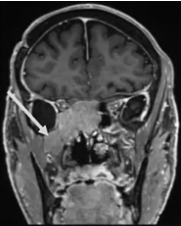

2012年,53岁的Leo突然发现自己嗅觉减退、视力下降时,就医检查发现右侧梅克尔腔脑膜瘤,随即进行了手术。谁能想到7年过后,脑膜瘤再次卷土重来,出现严重的V1(嗅神经)、V2(视神经)和V3(动眼神经)感觉减退和疼痛,症状比第一次手术前还要严重。磁共振成像(MRI)显示肿瘤大面积复发,延伸至海绵窦(CS)、后颅窝(PF)、蝶窦(SS)、翼腭窝(PPF)和颞下窝(ITF)。这个张牙舞爪的肿瘤,属实不太容易切除。

患者术前影像。(A)术前轴位T1加权钆增强磁共振成像(MRI),显示脑膜瘤延伸至后颅窝、海绵窦、眼眶和蝶窦。(B)肿瘤延伸至中颅窝、翼腭窝和颞下窝。(C)术前轴位计算机断层扫描(CT)显示蝶骨大翼侵蚀和蝶窦受累。

最终,手术顺利完成,根据术前术后影像对比,患者肿瘤得到完全切除。